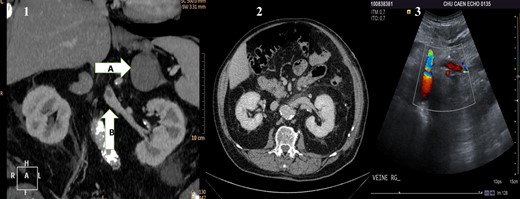

(1) Preoperative CT scan showing the adrenal mass (A) and in the renal vein a hypodense mass (B) corresponding to the renal vein tumor thrombus. (2) Postoperative CT scan showing the left kidney and its permeable vein. (3) Flow in the left renal vein on postoperative Doppler ultrasound.

The postoperative management was simple except for an Aeromonas hydrophila pulmonary infection, which was successfully treated by a 15-day cure of antibiotics. The patient was discharged on Day 15. Histopathological studies revealed a 7-cm ‘round’ cells undifferentiated tumor with a vein tumor thrombus. No adjuvant treatment was proposed because there was no relation with the lung carcinoma, and tumor's resection margins were negative. The postoperative CT scan showed no thrombus in the left renal vein (Fig. 1). Doppler ultrasound performed 1 month after adrenalectomy proved a good left renal vein flux (Fig. 1). At 36 months of follow-up, the patient is alive without signs of recurrence.

A 74-year-old man was referred in December 2011 to our hospital for an adrenal mass, discovered during the follow-up of a pT3-N1 M0 large cells neuroendocrine lung carcinoma, treated in June 2011 by surgery. The lobectomy had been followed by four adjuvant cures of carboplatin GP 16. His main past medical history was hypertensive cardiopathy and non-insulin-dependent diabetes mellitus. On a clinical point of view, he had no symptoms and in particular no general physical deterioration. The computed tomography (CT) scan showed a left adrenal mass (7 × 10 cm enhanced with contrast) associated with a renal vein tumor thrombus (Fig. 1). A positron emission tomography scanner showed adrenal mass and renal vein tumor thrombus hypermetabolism proving their tumoral hallmarks. Surgical treatment was decided after anticoagulation treatment initiated (continuous intravenous administration of sodic heparin at the dose of 500 international unit/kg/day); after a left subcostal incision, the left colon was mobilized and the retroperitoneal space approached. Once the adrenal gland was visualized, its main vein was isolated and followed until the renal vein to localize the tumor thrombus. Using kidney cancer surgical technique for vena cava thrombectomy, we isolated all the confluents to the renal vein. After quadruple clamping (renal vein X2, spermatic vein and lumbar vein), the left renal vein was laterally opened in order to perform the thrombectomy, and the main adrenal vein was cut. Total clamping time was 12 min with no arterial clamping and no renal cooling required. The renal vein was washed with a heparinized saline solution and closed with a polypropylene 6/0 running suture. Then, the veins were unclamped, and finally the adrenal gland was removed with macroscopically disease-free margins taking away the adrenal fat along the upper renal pole capsule.